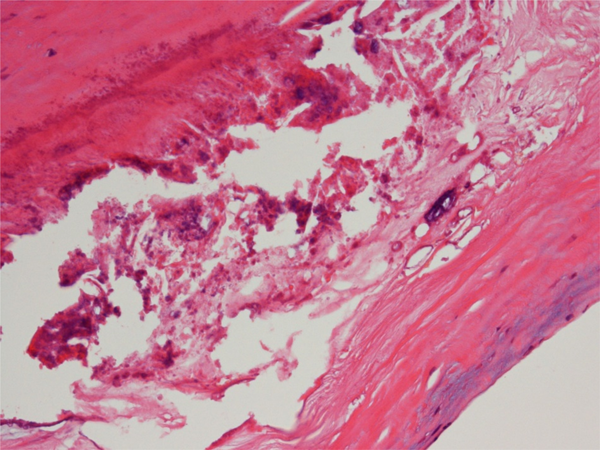

Fig. 3 Hematoxylin and eosin staining of the giant aneurysm at segment 5 removed (×200)

Thickening of intima and atherosclerosis-like lesions, such as accumulation of foam cells, hyalinization, needle-like cholesterol crystals, and granular calcification are observed.

A 38-year-old man, diagnosed with KD at age 7, was admitted to our hospital with a giant coronary aneurysm. Medical data on the initial KD diagnosis were not available. However, the coronary angiography at 2 years old showed that coronary aneurysms were observed at segment 1, 2 and 5. He was treated at our hospital until the age of 13, but there were no hospital visits since then. At his current admission, he was transported to previous hospital because of sudden chest pain. The blood test showed that creatine phosphokinase was 638 IU/L and an asynergy at inferior wall was observed with echocardiography while the cardiac function was normal. T-wave abnormality or the other specific findings of acute coronary syndrome were not seen with electrocardiogram. He was suspected with myocardial infarction. With the coronary angiography, the right coronary artery was dilated on the whole and a giant coronary aneurysm was observed at the left coronary artery while there were no stenoses (Fig. 1A, B). His condition improved with heparin and nicorandil and he was discharged under the treatment with oral clopidigrel and warfarin. Two weeks later, he complained of chest pain again, and was transported to the hospital. The blood test showed not elevated creatine phosphokinase but slightly elevated troponin T. The cardiac CT had located a giant coronary aneurysm, three calcified lesions, and the obstruction of a coronary artery by a thrombus. His Agatston score, which assesses the severity of CAC using the cardiac CT calculated with the CT levels more than 130 HU and their areas, and which is strongly associated with the cardiovascular event onset, was 1622.5 (left main trunk, 1579.4; left circumflex coronary artery, 0; left anterior descending artery, 0; right coronary artery, 43.1) (Fig. 1C).4, 5) He was diagnosed with myocardial infarction again. After his symptom rapidly improved with heparin and nicorandil, he was transferred to our institution for the operation. At the time of admission, his body weight was 113 kg, with a body mass index of 36.9 kg/m2. His morbid obesity was complicated with hypertension (systolic/diastolic blood pressure, 146/45 mmHg at admission), which we treated with 20 mg/day of azilsartan medoxomil; and hyperlipidemia (total serum cholesterol, 155 mg/dL; total serum triglycerides, 349 mg/dL) which we treated with 5 mg/day of rosuvastatin. The patient underwent a thrombectomy and coronary artery bypass grafting (left internal thoracic artery to obtuse marginal coronary artery and right internal thoracic artery to left anterior descending artery, segment 8) (Fig. 2). The giant aneurysm was removed because it triggered blood clots and they flowed into the periphery of the coronary artery, which caused myocardial infarction during surgery. Pathological examination revealed atherosclerosis-like lesions, including the accumulation of foam cells, hyalinization, cholesterol clefts, and granular calcification (Fig. 3). After surgery, carotid ultrasonography and pulse wave velocity results were normal, which indicated that the patient did not have atherosclerotic lesions or calcifications in the other arteries. Composition analysis with infrared absorption spectrometry revealed that the CAC was composed of >98% calcium phosphate with carbonate, similar to carbonate apatite (Fig. 4). The dual-energy CT showed that the median EANs of the calcifications was 13.41 (11.14–16.38), which resembled the EAN of CAC caused by atherosclerosis, 13.8 (Fig. 5).6) These results indicated that the composition of KD-induced CAC was similar to that of atherosclerosis. The patient has not exhibited any complications after the surgery, as confirmed by a post-operative follow-up of 6 months.